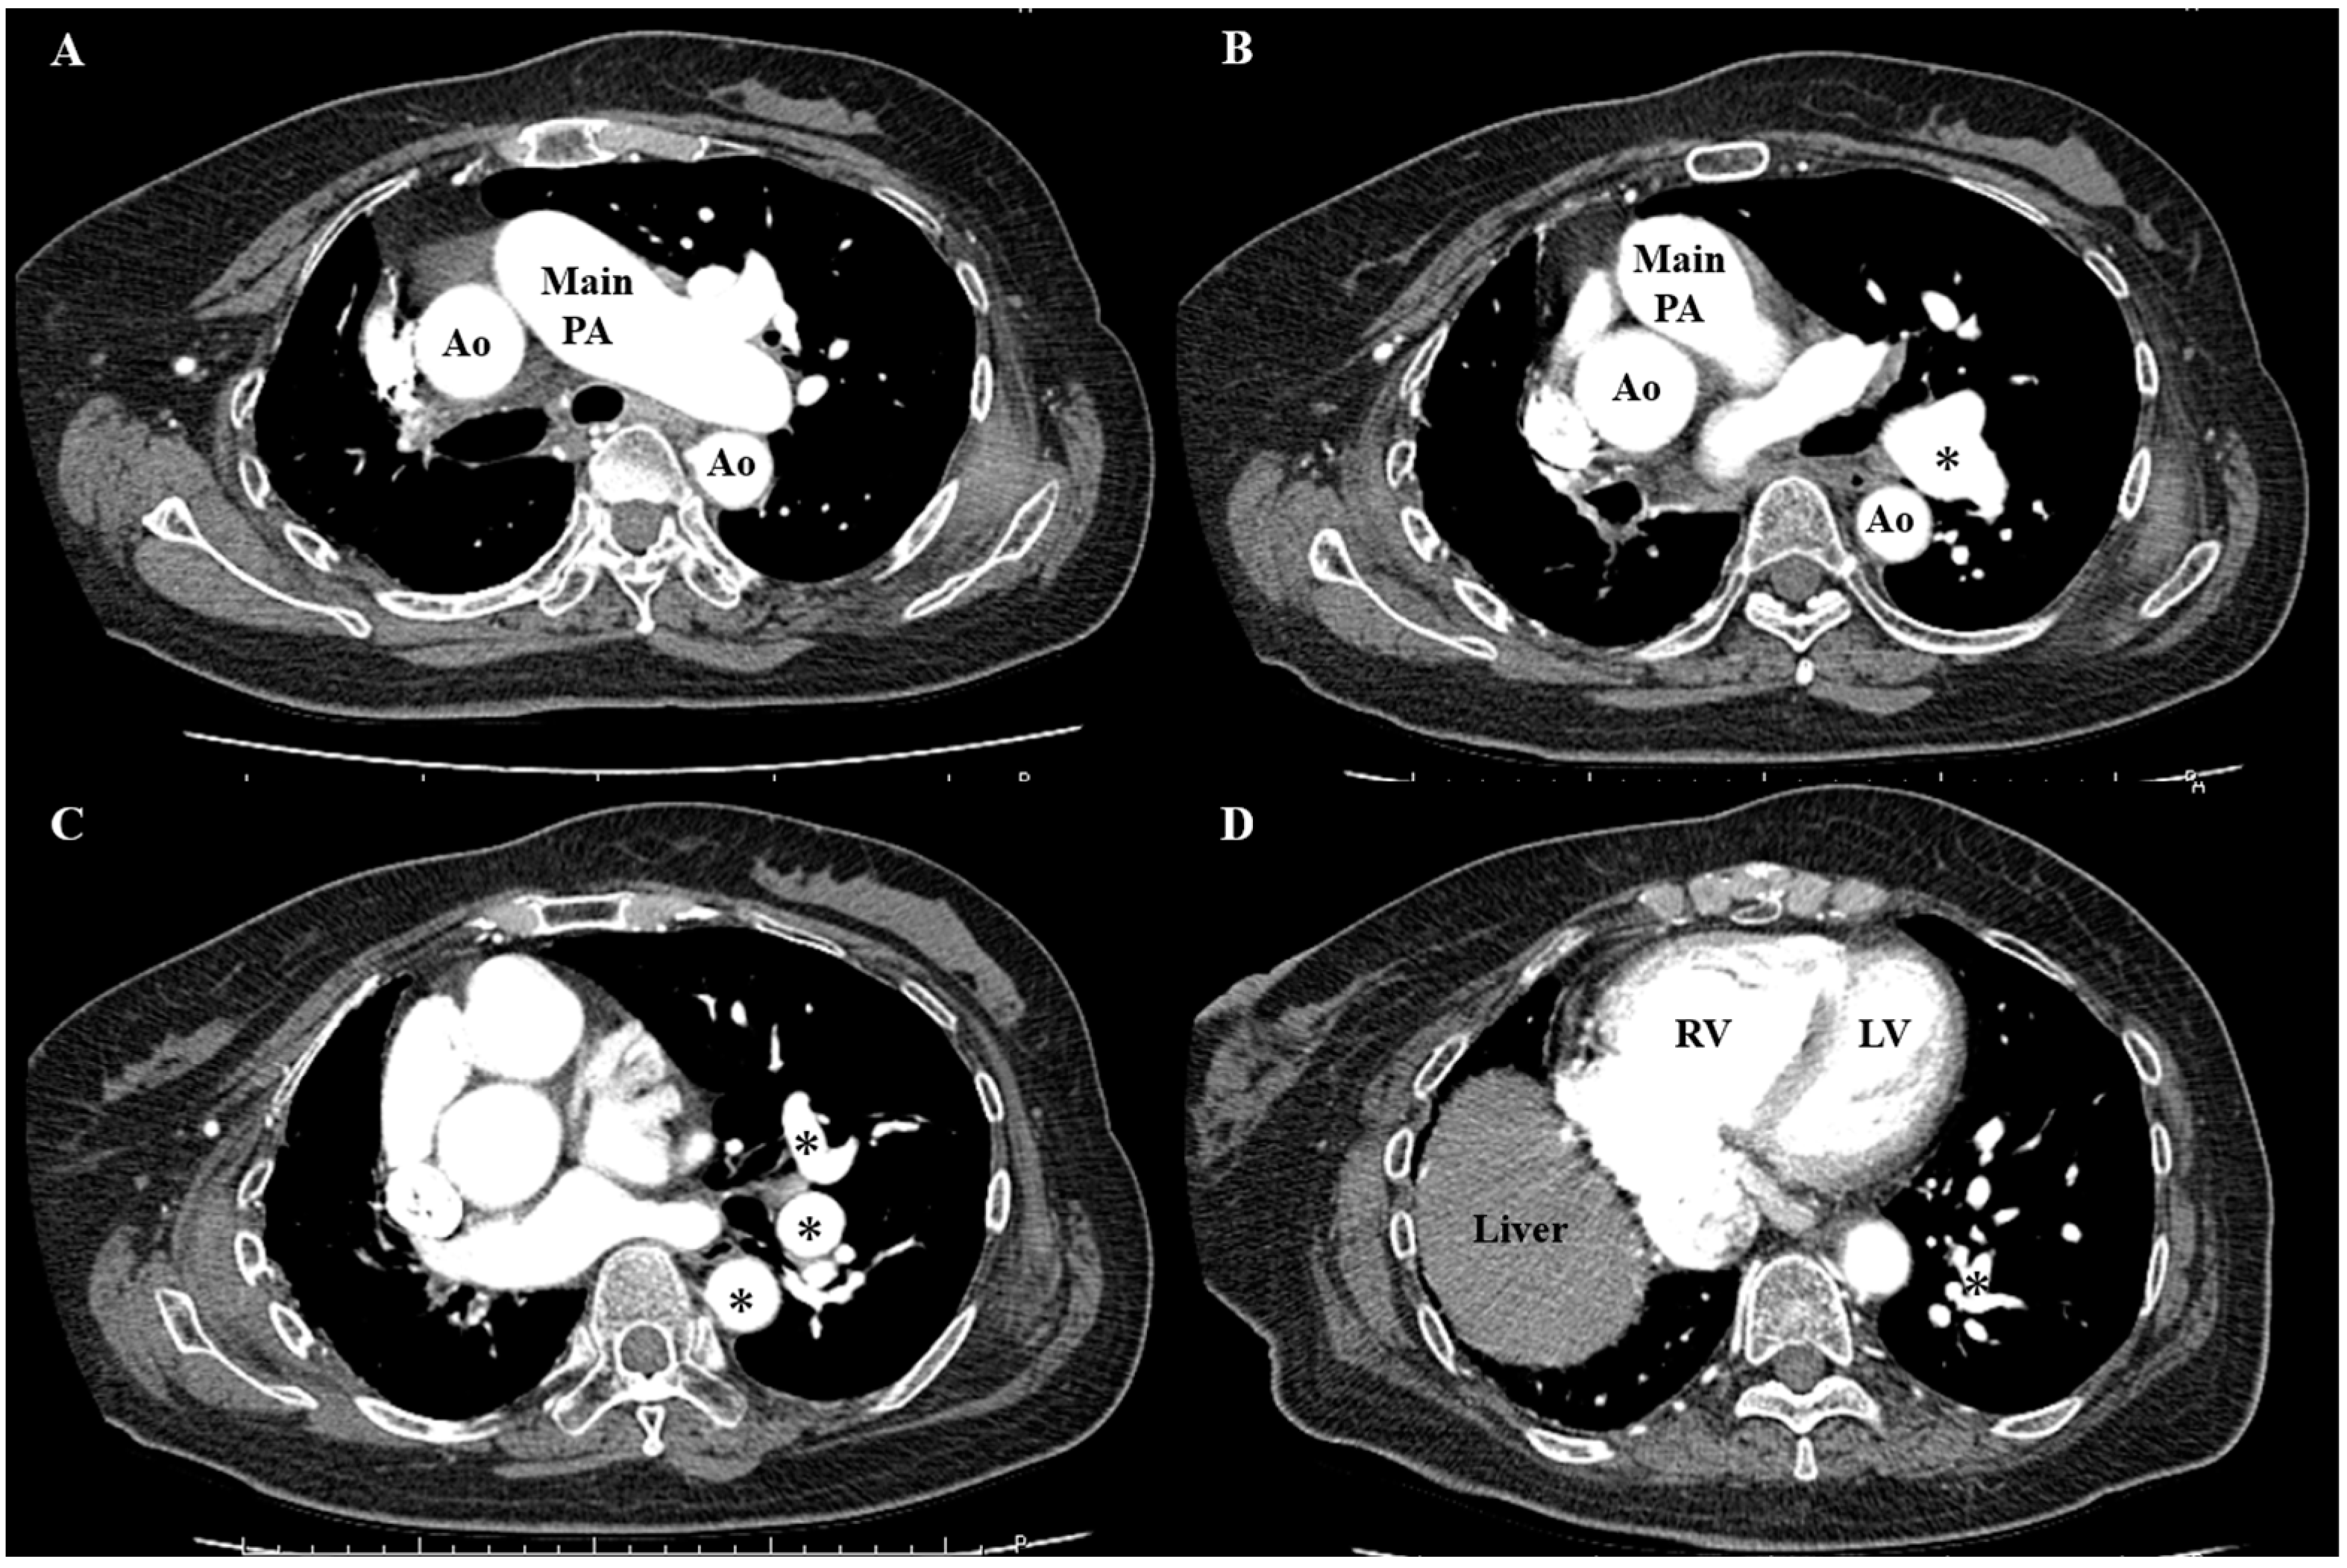

2.2. Investigation